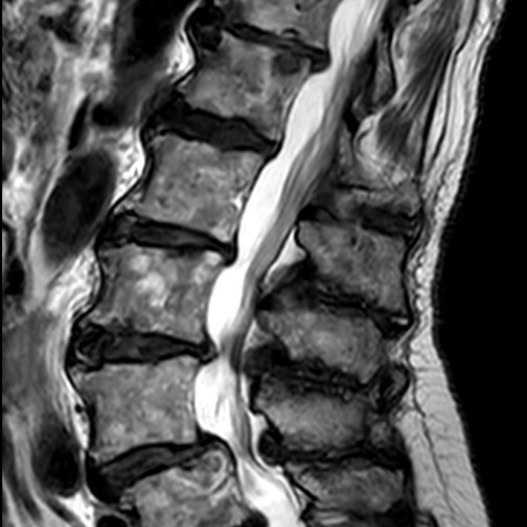

04.Advanced 3T MRI

Whole Body Scan

$2,800

We’re a doctor-owned, radiologist-led clinic using Australia’s most advanced 3T MRI technology. Every scan is interpreted by sub-specialist radiologists for the highest level of accuracy and care. Your experience is also uniquely designed for comfort, with immersive visual media to help you relax and feel at ease throughout your scan.